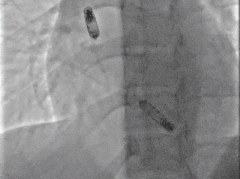

以上两位患者均以标准流程成功植入Aveir™ DR,最终固定位置影像:

病例2 RAO